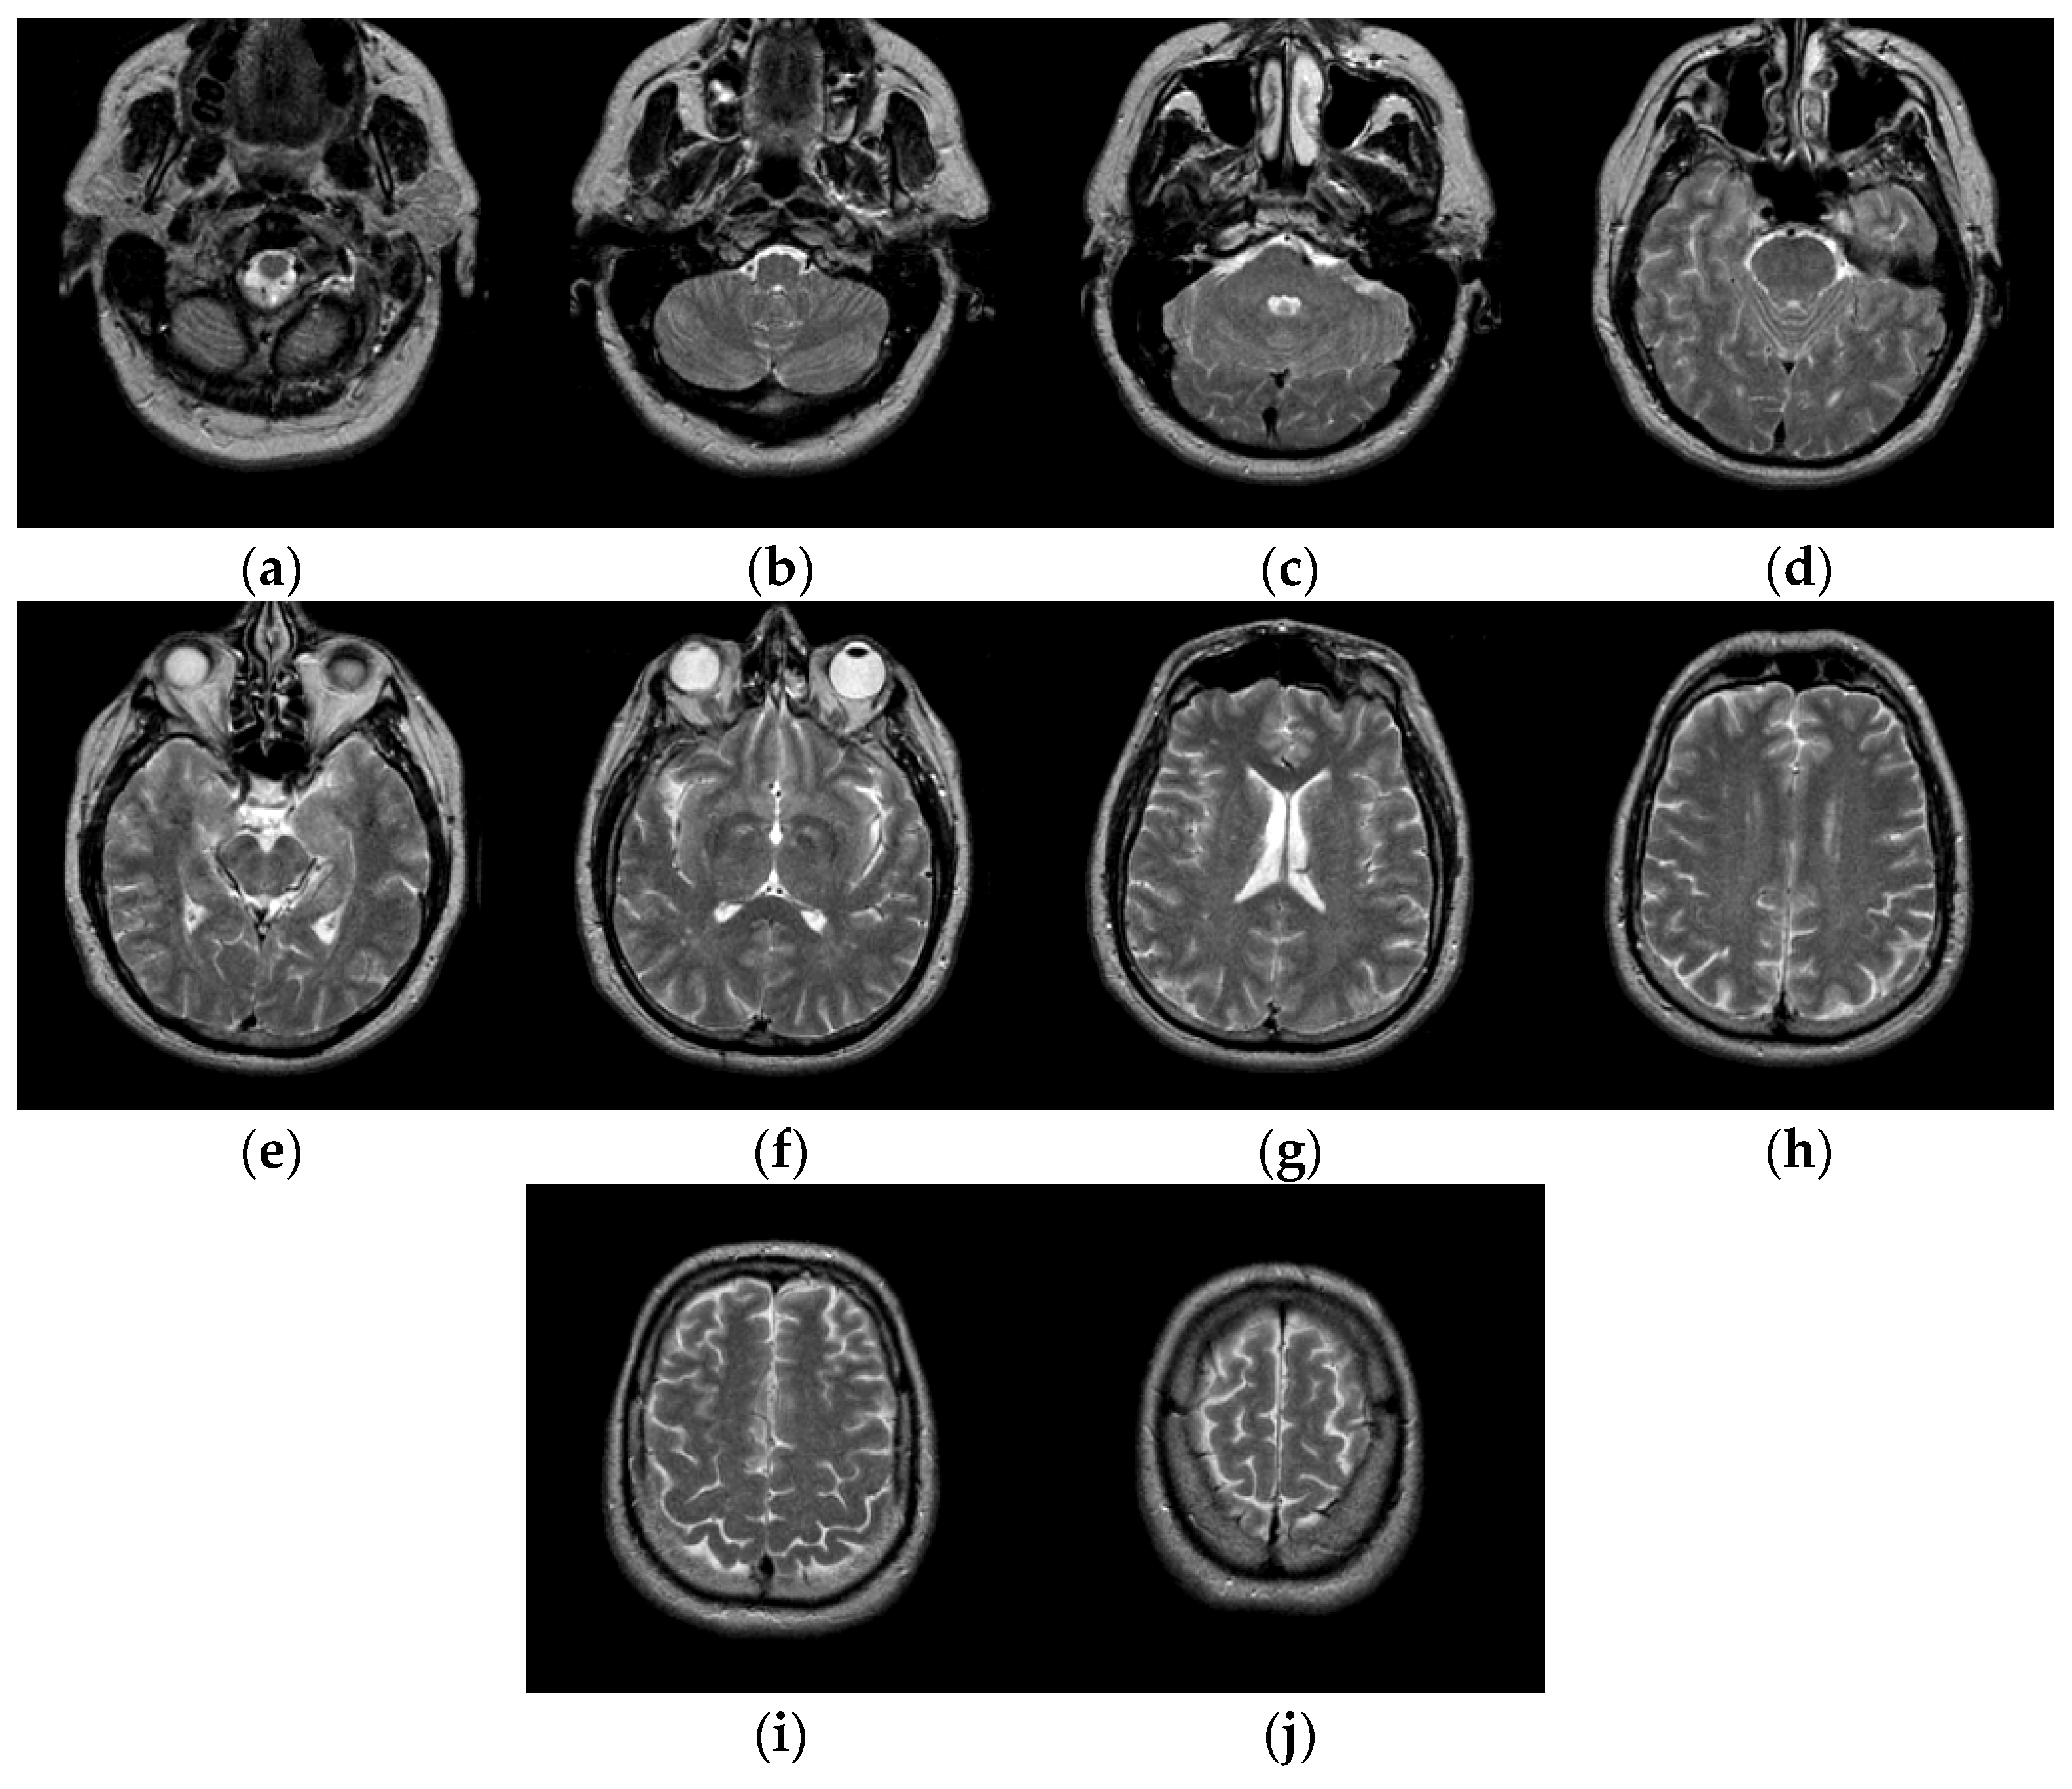

Figure 6 shows the results of two test images processed by the proposed hybrid spatial filter. It can be seen that the images after hybrid spatial filtering are smoother. The noise has been removed, and the details and structural information in original images are well preserved.

Figure 6.

An example of hybrid spatial filter. (a) Original images, (b) Part of the enlarged original images (c) The results obtained by hybrid spatial filter, (d) Part of the enlarged results images.